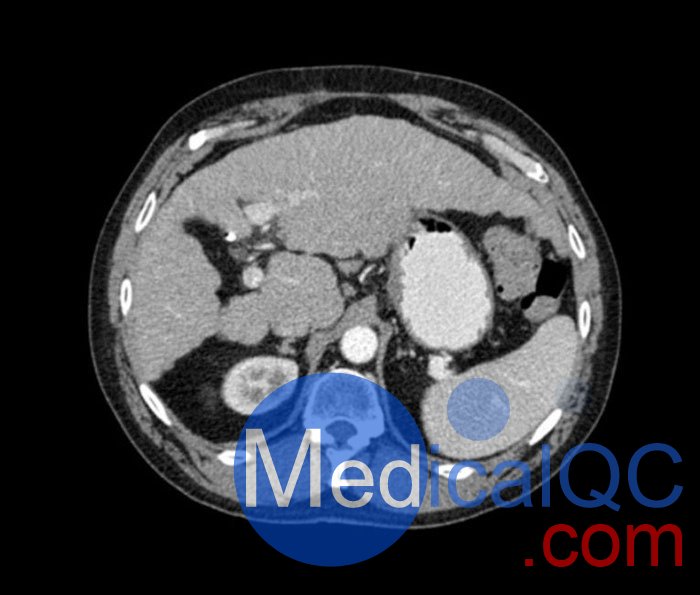

WEK53-04肝硬化腹部模體,WEK53-04腹部模體代表膽囊切除術(shù)后的腹部,帶有小夾子。肝臟有肝硬化的典型體征,在第三腰椎水平植入下腔靜脈過濾器。兩個腎臟都有囊性病變,左側(cè)有一小塊腎結(jié)石。

真實模擬脈管系統(tǒng)、骨骼和軟組織,包括肝臟、胰腺、脾臟、腎上腺、腎臟、胃、小腸和結(jié)腸。

• 肝硬化

• 膽囊切除術(shù)

• 下腔靜脈濾器